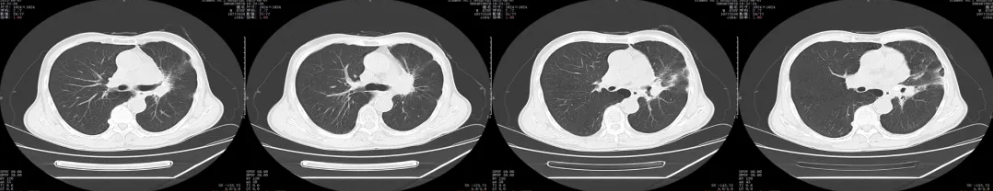

胸部CT平扫+增强:2023年复查

疗效评价:PR

胸部CT平扫+增强:2024年复查

疗效评价:SD